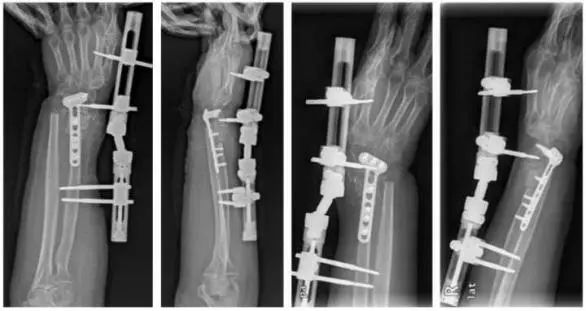

病例二

诊断:陈旧性桡骨远端骨不连,假关节形成,桡腕关节已融合。

治疗:骨不连假关节处植骨融合钢板内固定,尺骨短缩,单边外固定器固定。因桡腕关节已融合,故将单边外固定器反向应用。